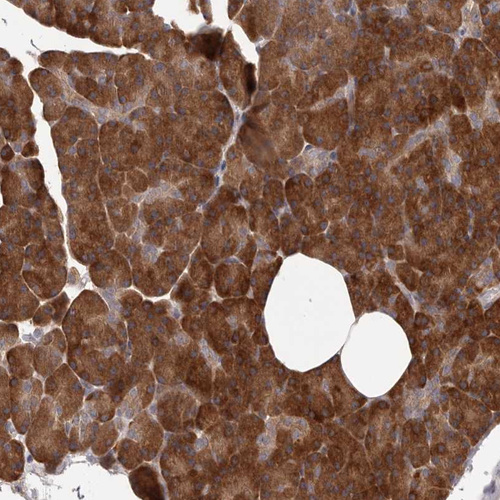

Immunohistochemical staining of human skeletal muscle shows strong cytoplasmic positivity in myocytes.